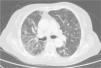

Clinical CaseThe patient is an 83-year-old woman with a history of hypertension treated with amlodipine 5mg/day, chronic kidney disease stage III, secondary to nephrosclerosis (GFR 45ml/min) and chronic treatment of polymyalgia rheumatica with methotrexate 15mg/week, for 4 years approximately. In recent years she has shown good clinical and analytical stability, not requiring steroid therapy or adjustments to her regular medication. Six weeks before admission she progressively presented fatigue, dyspnea, cough, and weight loss of 5kg. She had no fever, joint pain or muscle weakness. On admission, dyspnea at rest was observed with a baseline oxygen saturation of 90%, pulmonary auscultation showed bilateral fine crackles, with no palpable lymphadenopathy or organ enlargement, elevated erythrocyte sedimentation rate of 69mm C-reactive protein 3.5mg/dl and a chest X-ray which highlighted a diffuse and asymmetric bilateral reticular infiltrate with peripheral involvement, worse on the bases and on the right upper lobe (Fig. 1). After making a differential diagnosis of subacute lung disease in the context of methotrexate use, our main approach was to discontinue treatment, start steroids intravenously 48mg/day of methylprednisolone, and support measures, without clear improvement. A high resolution chest CT scan (HRCT) was performed, showing patched interstitial thickening of peripheral predominance in the lung bases and small nonspecific mediastinal lymphadenopathy (Fig. 2). The pulmonary function tests showed forced spirometry values in the low limit of normal, with a forced vital capacity (FVC) 1340ml (82%), a volume of expiratory flow after one second (FEV1) of 1130ml (88%) and an FEV1/FVC ratio of 84%, associated with a severe decrease in lung diffusion of carbon monoxide (DLCO) of 33% and corrected for an alveolar volume (KCO) of 54%. In the rest of the complementary tests, no changes were seen in the blood count, serology for atypical pathogens, the study of tumor markers, blood cultures, the serial study of sputum or the Mantoux/Booster test, so a bronchoscopy was performed with bronchoalveolar lavage (BAL) and led to a positive result in polymerase chain reaction (PCR) testing for CMV associated with an increased rate of CD4/CD8 lymphocytes 3.47, with the rest of the study for common germs, tuberculosis, P. jiroveci and fungi being negative. The microbiological study detected IgG (+), IgM (−) for CMV and CMV viral load in plasma (+), so treatment was initiated intravenously, adjusted for renal function, with ganciclovir 300mg/12h for 14 days, then changing to valganciclovir 900mg/12h orally for 14 days, with good tolerance and clinical response, with improvement in radiological, serological (CMV viral load undetectable) and respiratory function parameters (57.52% DLCO, KCO 80.90%, FVC 1950ml [119%] and FEV1 of 1680ml [130%]).